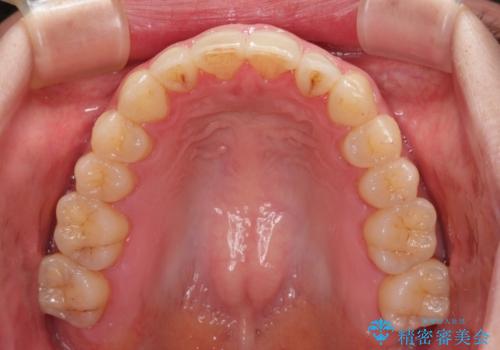

- 上下前歯の隙間を気にして来院された患者様です。

下顎前歯が1本欠損しており、上下小臼歯はクロスバイトとなり、上下前歯の接触もないという不正咬合の状態でした。

クロスバイトはワイヤー矯正が得意とするところであり、上下前歯の非接触や開咬はインビザラインの得意とするところであるので、ワイヤー装置により事前にクロスバイトを改善し、その後にインビザラインにて仕上げていくこととしました。